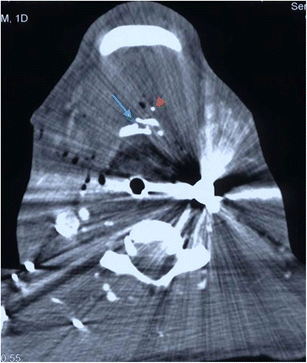

Axial MDCTA image through the infratemporal fossa of a 59-year-old man who fell on to a garden bamboo stick (thin blue arrow) which penetrated the left buccal region of the facial soft tissues, lodging and breaking-off in the retropharyngeal region of the nasopharynx and causing dissection occlusion of the right internal carotid artery (note the normal contralateral left internal carotid artery [blue arrowhead]). The geometric margin of the air-containing abnormality highlights the radiologic features consistent with an embedded foreign body fragment of organic material (wood). The patient subsequently developed a near-total thromboembolic right middle cerebral artery territory infarct (imaging not shown)